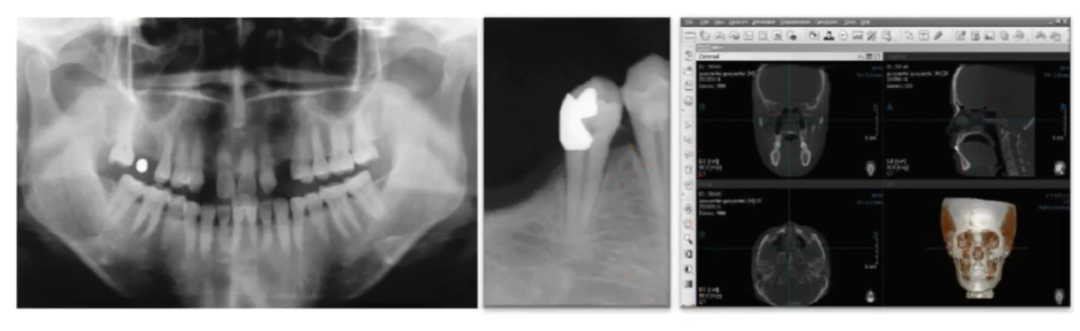

CBCT具体测量方法和容易陷进去的误区

CBCT用十字交叉法测量骨数据,可精准应用于双皮质固位。但有时CBCT也会让人判断不清骨缺损或骨密度低,例如下图:拍了CBCT并进行了重建,发现骨缺损,但牙槽嵴顶丰满度良好,这是因为拔完牙后骨密度还没有形成,但旁边牙齿骨密度高,对比太明显,CT把密度低的部分剪掉了,结果显示缺损,可以拍侧貌图3,可以看到轮廓,完全可以种植,所以一定要准确判断骨缺损还是骨密度低。